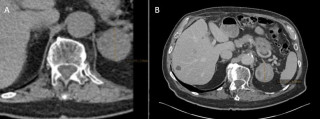

A 45-year-old man with no relevant past medical history presented with acute diffuse abdominal pain following a forceful sneezing episode. Physical examination revealed localized right-sided abdominal tenderness without peritoneal signs. Laboratory tests showed mild leukocytosis with normal inflammatory markers and hemoglobin. Contrast-enhanced computed tomography demonstrated a mesenteric hematoma associated with moderate hemoperitoneum and focal mural hypoenhancement of an ileal loop, without active arterial extravasation (Figure 1). Urgent surgical exploration revealed approximately 500 mL of hemoperitoneum, a large mesenteric hematoma, and an adjacent intestinal pseudodiverticulum (Figures 2-3). Segmental small bowel resection including the diverticulum was performed. Histopathological analysis confirmed fresh mesenteric hemorrhage and pseudodiverticular changes without evidence of malignancy, vasculitis, or vascular malformation. The postoperative course was uneventful, and the patient remained asymptomatic at six-week follow-up.